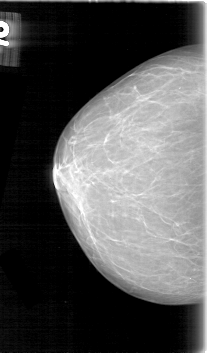

D_4060_1.LEFT_CC

LEFT_CC LINES 5386 PIXELS_PER_LINE 3301 BITS_PER_PIXEL 12 RESOLUTION 43.5 OVERLAY